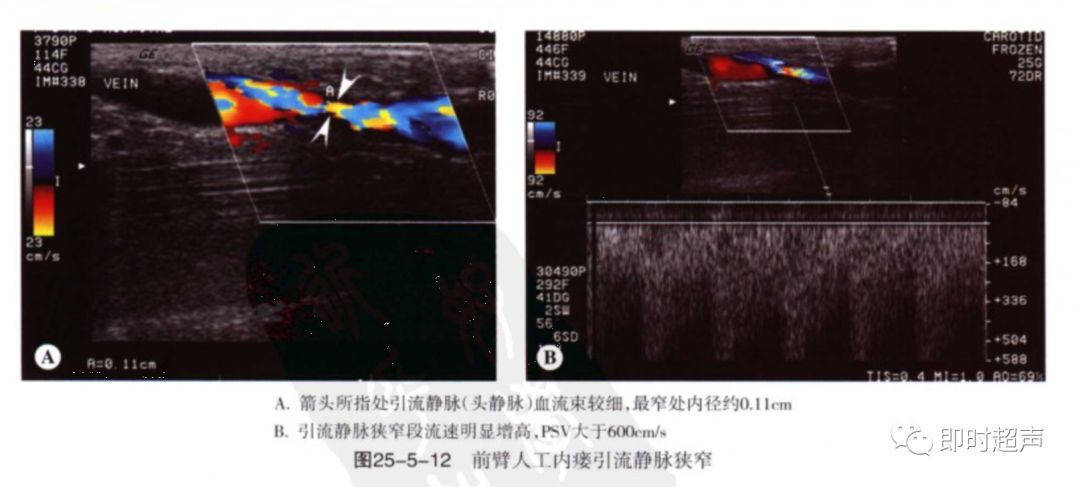

狭窄:狭窄大多发生于吻合口及静脉流出道。

超声表现:多普勒分析:狭窄处直接征象:PSV>4m/s(直径狭窄率50%以上),间接征象:供血动脉或肱动脉呈高阻波形,血流量减少。

(1)引流静脉狭窄:分别测量狭窄处及狭窄下游2cm处峰值收缩期流速,两者PSV比率≥2,提示存在≥50%狭窄。该方法影响因素:①是否有静脉属支引流导致流速降低②深浅静脉交通支开放影响③回心静脉出现问题 ④静脉瘤样扩张⑤瘘后静脉侧血流速度递减趋势对PSV测量的影响。

直径测量法:主要用于静脉流出道狭窄,但对静脉瘤样扩张处狭窄不适用。

狭窄%=(附近相对正常静脉血管内径-最窄处内径)/附近相对正常静脉血管内径×100%

吻合口内径正常约3-5mm,若小于2.5mm,血流异常考虑吻合口狭窄。